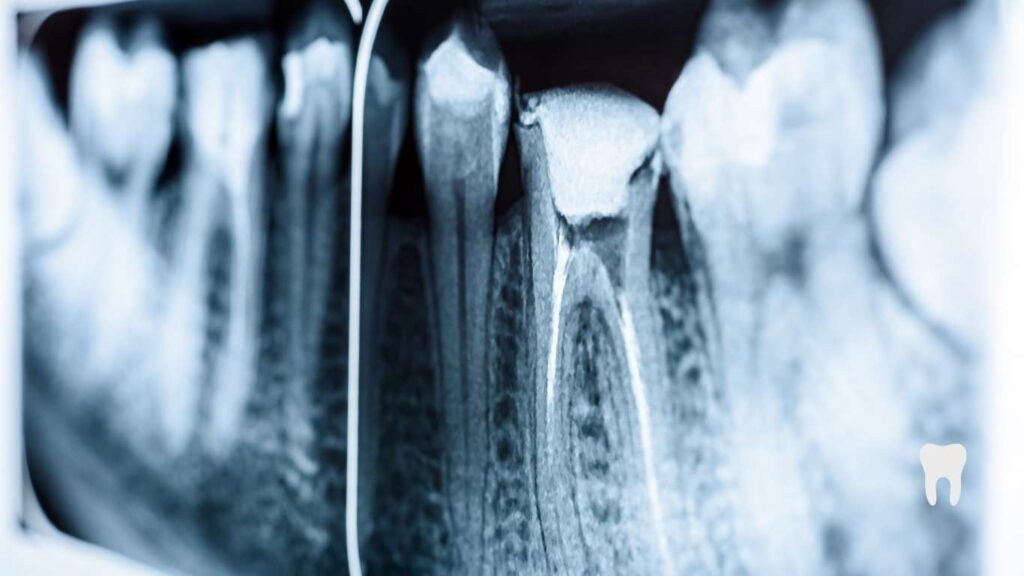

- Take digital X-rays (or sometimes CBCT scans) to view the internal anatomy

- Checking and rechecking with trial instruments and possibly with X-rays

Ensuring a good seal requires precision, possible adjustments, and possibly verification with X-rays. This step typically takes 15 to 40 minutes.